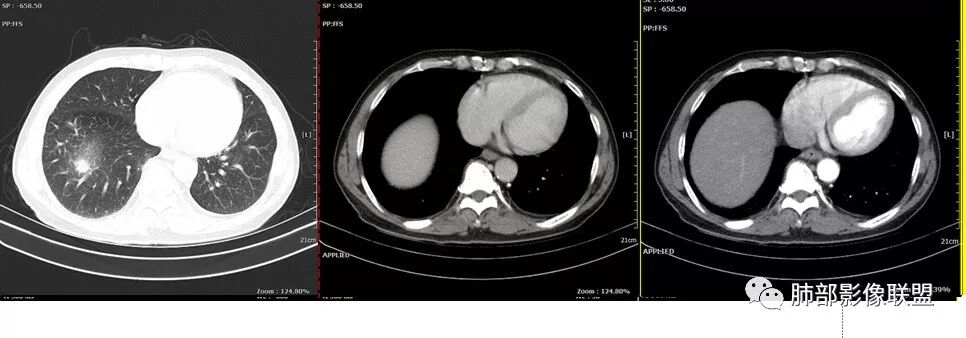

老年男性,有糖尿病4年,长期咳嗽;这次咳嗽5天,左胸痛2天

纵膈淋巴结以钙化为主。

这个壁厚,但是支气管软骨连续。

背段支气管有问题,局部有结节

膈面上还有一个结节

总共4处病灶,如何考虑?

左肺上叶病灶长轴与支气管走形一致,提示沿支气管分布病变,倾向于炎性,大家可能怀疑这个病例是来源于胸膜下为主的,胸膜下来源首先整体是来源于胸膜下,与胸膜下之间没有间隙,而这例与胸膜下有间隙。而且这个病变是沿支气管朝外蔓延的,而胸膜下来源的是朝内蔓延的,唯一给我们错觉的是靠近纵隔胸膜这个地方有问题。但是靠近纵隔胸膜这个位置实变不是靠近胸膜实变,它边缘收缩的,没有膨隆的迹象。我们看到里面支气管直达远端稍扩张,是以中央间质为主、小叶间隔朝外蔓延,有间质也有实质病变,走向是沿中央间质方向走的,我个人倾向炎性病变。    问题是右下叶病灶怎么解释?右隔上、右肺门各有一个结节。这个病人有急性咳嗽、胸痛的病史,还有糖尿病病史,周围渗出比较明显,应该警惕炎性病变,要警惕克雷伯杆菌、结核、金葡菌霉菌,因为糖尿病人经常好发这些病菌感染。那么右下叶病变怎么考虑?能不能一元论?    左肺病灶是一个急性渗出为主的病变,一个急性感染的迹象;右肺下叶背段结节,没有看到支气管,增强图支气管壁增厚,局部小结节,呈分叶状,支气管堵塞,没有粘液栓样指套样改变,但是里面有强化,我倾向于癌,其次待排结核。我还是倾向于癌的可能性,恶性可能性大一些,可惜我看不到支气管腔内。还考虑有没有淀粉样变性的问题,弥漫钙化灶最常见的一个是结核,另一个是淀粉样变性。叶段支气管壁有弥漫增厚的迹象。所以淀粉样变性跟结核都要考虑。

1.右肺下叶支气管壁增厚,后壁为主,且显示壁外结节,未见异常强化。这样的结节和蔓延方式一般会高度怀疑气道来源的恶性肿瘤,如鳞癌、粘液表皮样癌、腺样囊性癌等。可惜没有相应病理学资料支持。

右肺下叶近膈面球形病灶缺乏恶性病灶特点,没有分叶、毛刺、牵拉等,应当符合炎性。